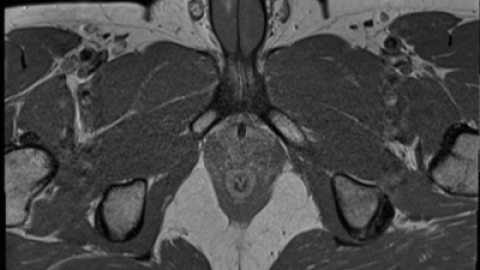

Por lo anterior, los expertos hicieron una resonancia magnética y confirmaron que el pene había sufrido una fractura vertical de tres centímetros de largo, en el lado derecho del miembro, y no un desgarro transversal, como ocurre en otros casos.